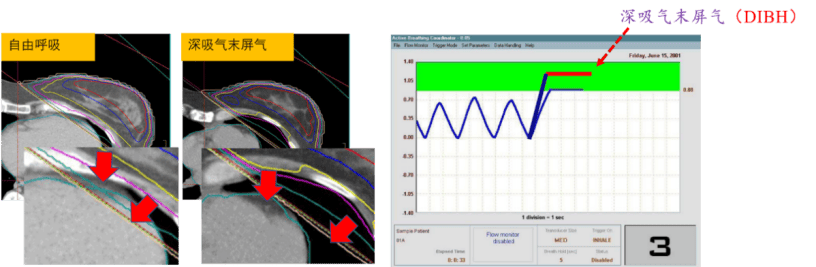

乳腺癌放疗中面临的心脏跳动、呼吸运动通常会导致放射性心脏损伤(Radiation-induced heart injury,RIHD),当患者的呼吸时相在深吸气屏气末阶段(Deep inspiration breath hold,DIBH),肝肾间隙,肺体积,胸壁-心脏间隙都可达最大化,在此时相内实施照射可明显减少放疗毒性反应。通过联合患者的深吸气屏气时相使用4D-CT的前瞻式扫描,对患者的深吸气屏气末时相进行阈值定义,射束只在DIBH时相出束,从而降低患者放射性心脏损伤和放射性肺炎的发生概率。

左侧乳腺癌患者的DIBH治疗